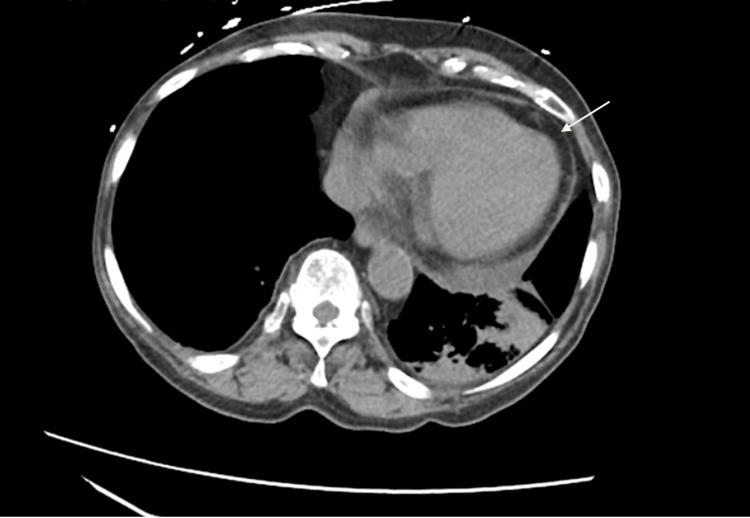

Meigs syndrome is a rare condition characterized by the triad of benign ovarian tumors, ascites, and pleural effusion. However, concurrent presentation with both pleural and pericardial effusions is exceedingly rare. This paper presents a unique case of Meigs syndrome in a 75-year-old African American female patient with a history of anemia who was admitted for a left femur fracture secondary to a fall.  In addition to her orthopedic injury, the patient exhibited intermittent abdominal fullness and discomfort, prompting a thorough diagnostic evaluation. Physical examination was unremarkable, and laboratory investigations revealed microcytic anemia with normal renal and hepatic function tests. Unexpectedly, imaging studies revealed the presence of a large lobulated enhancing mass lesion arising from the terminal ileum, with no evidence of ascites. Computed tomography (CT) imaging also revealed bilateral pleural effusions and a mild pericardial effusion. Initial diagnostic evaluations yielded no significant findings with normal CA-125 and CEA levels and no abnormalities in peripheral blood.  The pathophysiology underlying the development of pleural and pericardial effusions in Meigs syndrome remains unclear but is thought to involve lymphatic obstruction and increased vascular permeability secondary to the ovarian tumor.  In conclusion, this case underscores the importance of recognizing variant presentations of Meigs syndrome, particularly in the context of concurrent pleural and pericardial effusions, which may pose diagnostic challenges but warrant prompt identification and management to optimize patient outcomes.

梅格斯综合征是一种罕见病症,其特征为良性卵巢肿瘤、腹水和胸腔积液三联征。然而,同时出现胸腔积液和心包积液的情况极为罕见。本文介绍了一例独特的梅格斯综合征病例,患者为一名75岁非裔美国女性,有贫血病史,因跌倒导致左股骨骨折入院。除了骨科损伤外,患者还表现出间歇性腹部胀满和不适,促使进行全面的诊断评估。体格检查无异常,实验室检查显示小细胞性贫血,肾功能和肝功能检查正常。出乎意料的是,影像学研究显示回肠末端有一个大的分叶状强化肿块病变,无腹水迹象。计算机断层扫描(CT)成像还显示双侧胸腔积液和轻度心包积液。初步诊断评估未发现明显异常,CA - 125和CEA水平正常,外周血无异常。梅格斯综合征中胸腔积液和心包积液形成的病理生理机制尚不清楚,但认为与卵巢肿瘤继发的淋巴管阻塞和血管通透性增加有关。总之,该病例强调了认识梅格斯综合征变异表现的重要性,特别是在同时出现胸腔积液和心包积液的情况下,这可能带来诊断挑战,但需要及时识别和处理以优化患者预后。